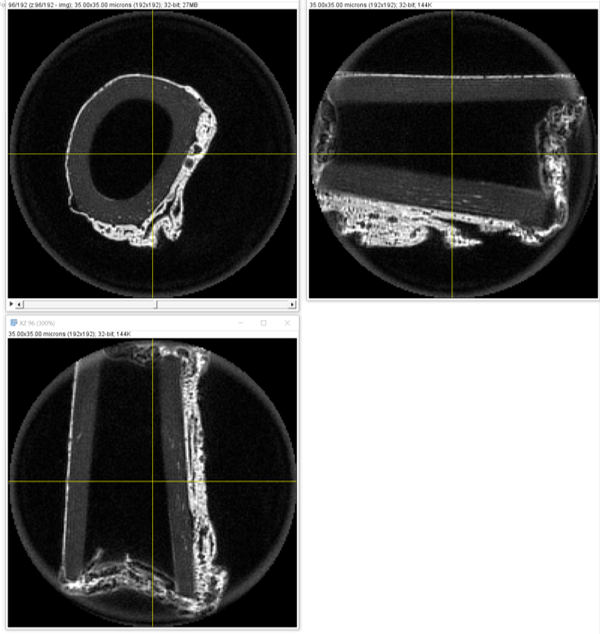

Sample Image of Cortical Bone (3 Views) at 7T

• UTE sequences at 7T preclinical MRI (Bruker) were implemented and acquired:

• Results for data acquisition shows UTE-MRI is capable to move to the extent of all the proton pools ex-vivo,